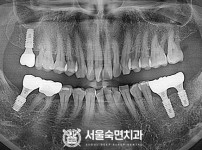

임플란트-전후사진3